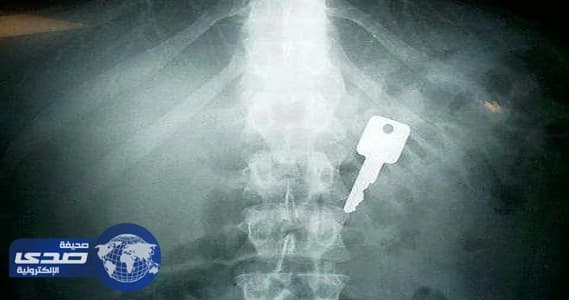

للأخطاء الطبية ضحايا كثر ،تشهد عليها العديد من مستشفيات المملكة ، والتي من أبرزها استخراج أجسام صلبة من أجساد مرضى مواطنين ومقيمين،كالشعر والملاعق والمسامير وأدوات جراحة أو كبسولات مخدرات.

ووفقا لتقرير نشرته صحيفة الحياة فإن مستشفى بريدة أيضا شهد ابتلاع طفل (سنة وأربعة أشهر) مسماراً، ما تسبب في انسداد مجرى التنفس العلوي، وعرض حياته للخطر، فيما ابتلع طفل آخر (ثمانية أشهر) كرة بلاستيك صغيرة الحجم أدت إلى اختناقه وتوقف قلبه.

و تعرض له مقيم هندي (24 عاماً)، حيث اخترق مسمار قلبه مرتداً من جهاز تثبيت آلي، وتمكن فريق طبي في مركز الأمير سلطان لجراحة القلب في القصيم من إنقاذ حياته، فيما ابتلعت مريضة وافدة ملعقة كادت تتسبب في وفاتها.